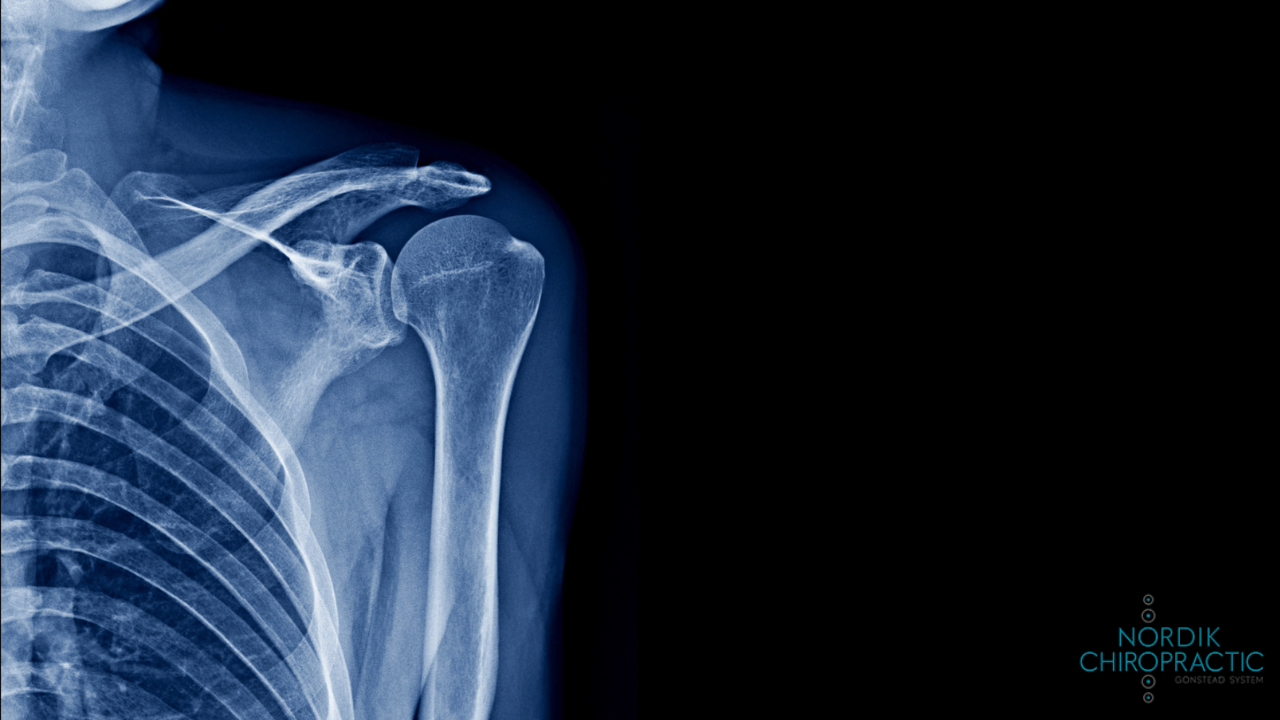

Using X-rays and the Nervoscope allows Nordik Chiropractic chiropractors to determine an issue accurately.

• X-rays to examine the spine in more detail

For example, using digital X-rays, spinal decompression therapy, and high-frequency adjustment tools allows for a biomechanical view of the spine, giving the doctors at Nordik Chiropractic insights into a patient’s disc integrity, misalignments, and postural imbalances.